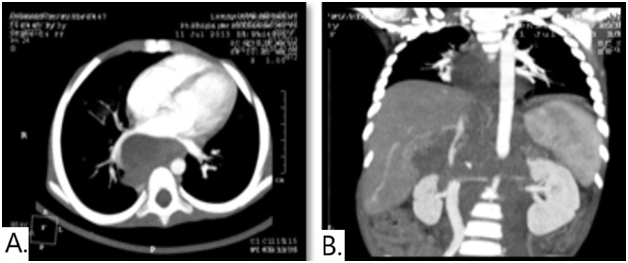

A 3 years old female child presented with complaints of high grade fever, abdominal mass and a left supraclavicular lymph node since 2 months. On examination, single left supraclavicular lymph node measuring 1x0.5 cm and distended abdomen with free fluid was observed. Ultrasonography of abdomen revealed a large, lobulated, heteroechoic, conglomerated nodal mass of size 11.3x8.3x7cm in retro peritoneum with multiple anechoic areas and ascites. On this basis, a clinical diagnosis of Non-Hodgkin’s lymphoma was made. FNAC performed from abdominal mass and lymph node showed similar cytomorphological features. Smears were cellular, showing single cells as well as poorly cohesive groups of large anaplastic cells with large, pleomorphic vesicular nuclei with 2 to 3 prominent nucleoli and scant to moderate amount of cytoplasm (Figure 1). Many binucleated and multinucleated tumor cells with presence of doughnut, embryoid, reniform and occasional wreath cells were identified (Figure 2). Many atypical mitotic figures were also seen. Based on these cytological features, a diagnosis of anaplastic large cell lymphoma was suggested. Meanwhile CT scan revealed a heterogenously enhancing retroperitoneal nodal mass measuring 11x8x7cm with encasement of major vessels & bowel along with single foci of calcification and chest involvement suggestive of lymphoma/neuroblastoma (Figure 3). Serum VMA level was also found to be raised (17.5mg/24hrs). Following this lymph node biopsy was done and the histopathology showed complete loss of architecture & replacement by tumor .The tumor cells were arranged in nests and cords separated by fibrous septae with occasional rosettes and absence of neuropil (Figure 4). The tumor cells were large, round to oval in shape with round to oval nucleus with moderate anisonucleosis, irregular nuclear membrane, coarsely clumped chromatin, 2 to 3 prominent nucleoli and scant to moderate amount of eosinophilic cytoplasm. The tumor cells show similar cytomorphological features as in FNAC smears and many atypical mitotic figures (03/Hpf) were seen. Immunohistochemical panel for LCA, CD15, CD30, ALK, SMA, synaptophysin, chromogranin and NSE was applied. The present case showed strong positivity for chromogranin and NSE, however was negative for all the other markers (Figure 5).

Figure 2 CT-scan showing heterogenously enhancing retroperitoneal nodal mass measuring 11x8x7cm with encasement of major vessels and bowel, single foci of calcification with chest involvement.